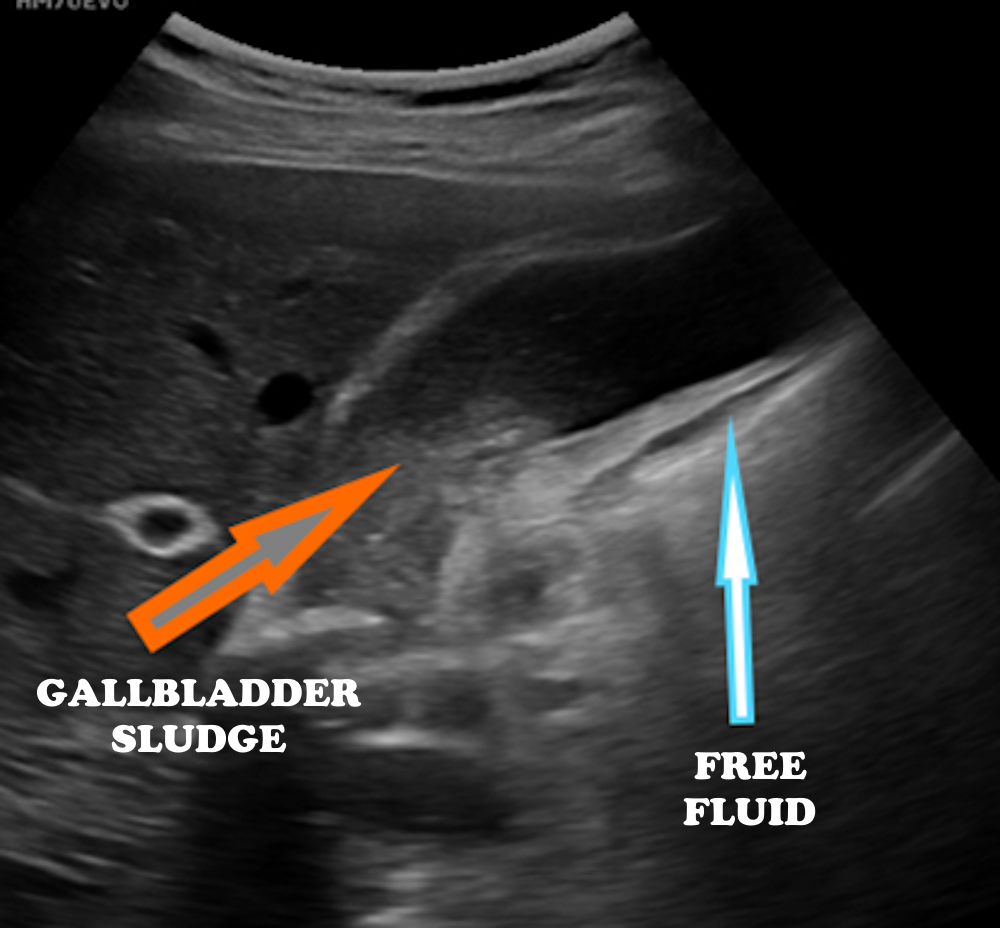

A normal gallbladder measures approximately 10 cm in length and 2–4 cm in diameter, with a wall thickness of less than 3 mm. Gallstones typically appear as hyperechoic foci that produce posterior acoustic shadowing (Figure 7). In acute cholecystitis, increased wall thickness, pericholecystic fluid, and a positive sonographic Murphy’s sign may be observed (Figures 7 and 8). In cases with biliary sludge, a homogeneous fine internal echogenicity is noted (Figure 8). Polyps appear attached to the gallbladder wall and do not move with changes in patient position (Figure 9). Visualization of the main portal triad during gallbladder ultrasonography is crucial for identifying hepatobiliary system pathologies (Figure 10).